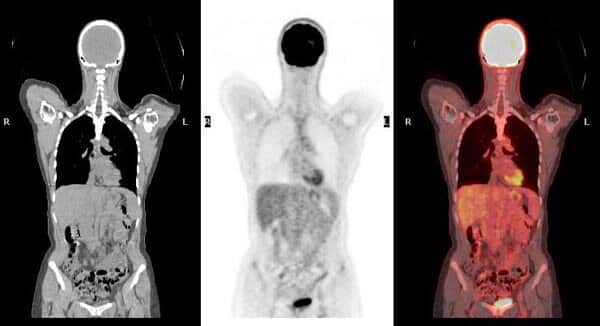

A DOTA PET scan is a specialised PET-CT imaging test that uses Ga-68-labelled radiotracers such as DOTATATE, DOTATOC, or DOTANOC to detect neuroendocrine tumors. This scan is different from routine PET scans and is performed only when advised by a doctor for specific clinical indications.

A DOTA PET scan is a specialised PET-CT imaging test used to detect and evaluate neuroendocrine tumors by targeting somatostatin receptors present on tumor cells. It uses a DOTA-based radiotracer that binds specifically to these receptors, allowing precise visualisation of disease activity.

A DOTA PET scan works by using a radiotracer that binds to somatostatin receptors present on certain tumor cells. After the tracer is administered, it circulates through the body and attaches to receptor-positive tissues, allowing precise imaging of tumor activity.

The PET-CT system then captures detailed images that help doctors assess tumor location, spread, and receptor expression, supporting accurate diagnosis and treatment planning.